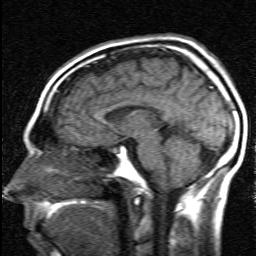

Some new photos. Same caveat that I know Instill have hair. But Jesus if you look at my baseline and you calculate under three years, 2.5 full years in oral minoxidil and 15 months on topical Finasteride I am definitely fucked. Now I’m mixing in HCG to try and at least recover my health because nothing has slowed down this nightmare train. It Seems like the crown which was the first to thin is better than then forelock and hairline.

Would you same I’m a NW2 diffuse at this point? Worse? Are the hairline hairs already miniaturized? Would an expensive FUE even work for me in a few years if I gave up treatment now or will I need to be on Finasteride/Dutasteride even for that?

included 2 baseline pics from November 2016 and March 2017 for density reference.